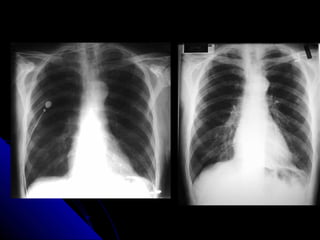

IInnssppiirraattiioonn EExxppiirraattiioonn

TThhee lleevveell ooff iinnssppiirraattiioonn ccaann bbee eessttiimmaatteedd

bbyy ccoouunnttiinngg rriibbss.. VViissuuaalliizzaattiioonn ooff nniinnee

ppoosstteerriioorr rriibbss,, oorr sseevveenn aanntteerriioorr rriibbss oonn aann

uupprriigghhtt PPAA rraaddiiooggrraapphh pprroojjeeccttiinngg aabboovvee

tthhee ddiiaapphhrraaggmm wwoouulldd iinnddiiccaattee aa

ssaattiissffaaccttoorryy iinnssppiirraattiioonn..